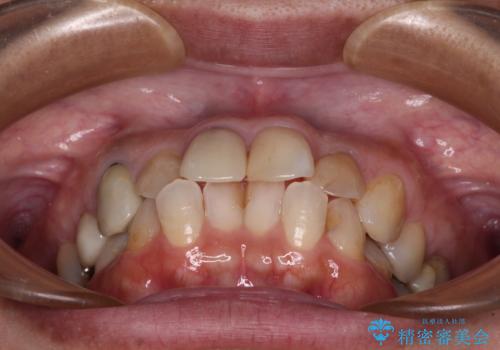

- 上下前歯のデコボコを気にして来院された患者様です。

歯列としては、ワイヤー装置でもインビザラインでも、どちらでも対応可能でしたが、処置されている歯が多く、ワイヤー装置を装着するためには処置歯のやり直しが必要な状態でした。

インビザラインでもアタッチメントを装着できないという同様のデメリットがありますが、比較的矯正治療を行いやすい歯列であったので、インビザラインによる矯正治療を行うこととしました。